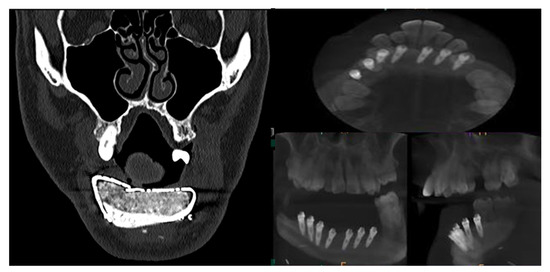

CT Scan and CBCT were performed in the postoperative follow-up, and bone volume and bone resorption (Figure 13 and Figure 14) were evaluated by the Radiology Department of the hospital. A morphing reconstruction was performed to compare the lower facial third showing an improvement in the aesthetic profile and facial projection (Figure 15).

Figure 13. CT Scan and CBCT were performed in the postoperative follow-up, providing relevant quantitative data regarding bone volume and bone resorption.

Jcm 10 01922 g013

Figure 14. CBCT performed in the follow-up to evaluate bone resorption before and after implant loading.